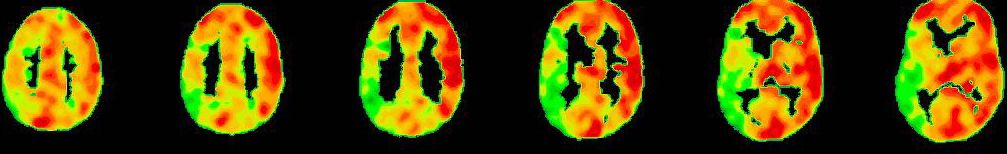

Wissenschaftliche Abbildung

PET/CT mit Darstellung der einseitig reduzierten Reservekapazität/Durchblutung (kalte Farben) im Vergleich zum physiologischen Anstieg der Perfusion auf der Gegenseite (warme Farben).

PET-CT nach Diamox Gabe

PET-CT nach Diamox Gabe zeigt eine einseitig deutlich reduzierte Perfusionsreserve (grüne Farben) im Vergleich zur Gegenseite mit ausreichendem Anstieg der Durchblutung (warme Farben).